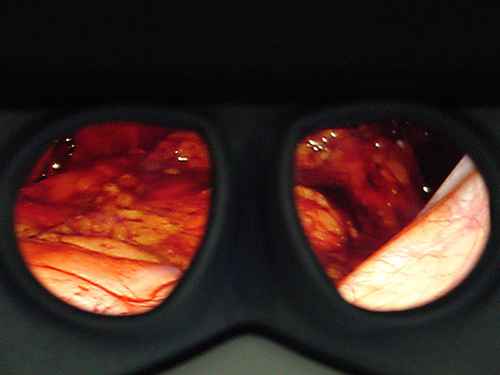

Η ακρίβεια των χειρισμών, η δυνατότητα να υπάρχουν μέσα στην κλειστή κοιλιά του ασθενούς δύο μικροσκοπικά χεράκια που εκτελούν με την ίδια και μεγαλύτερη ευλυγισία και ελευθερία τις κινήσεις του ανθρώπινου καρπού, η μεγεθυμένη και τρισδιάστατη εικόνα και ο έλεγχος που παρέχει το ρομποτικό σύστημα da Vinci συμβάλει στην αφαίρεση του προστάτη, που έχει προσβληθεί από καρκίνο, διατηρώντας ταυτόχρονα τα σπουδαία στυτικά νεύρα και αιμοφόρα αγγεία.

Επιπλέον ο χειρουργός ελέγχει μία στεροσκοπική οπτική που συνδέεται μία υψηλής ευκρίνειας κάμερα η οποία εξασφαλίζει μία τρισδιάστατη υψηλής ευκρίνειας όραση της εσωτερικής ανατομίας του ασθενή. Ένας έμπειρος χειρουργός λειτουργεί σαν βοηθός και στέκεται δίπλα στο χειρουργικό τραπέζι βοηθώντας τον ρομποτικό χειρουργό κρατώντας ανοιχτό το χειρουργικό πεδίο, αναρροφώντας και καθαρίζοντας, χρησιμοποιώντας όργανα που εισέρχονται μέσα από τα δύο βοηθητικά τροκάρ.

Σχηματική απεικόνιση σε πραγματική φωτογραφία της εντόπισης του αγγειονευρώδους δεματίου στη πλάγια επιφάνεια του προστάτη έτσι όπως φαίνεται από την πάνω κοιλιακή άποψη του προστάτη.

Η υψηλής ευκρίνειας τρισδιάστατη όραση και η μεγέθυνση 10-15 φορές επιτρέπουν στον χειρουργό να βλέπει και τον καρκίνο και τους υγιείς ιστούς και τα αιμοφόρα αγγεία σε τέτοιο επίπεδο μεγέθυνσης και λεπτομέρειας που είναι πολύ ανώτερο από εκείνο που προσφέρει η ανοιχτή χειρουργική ή η συμβατική λαπαροσκοπική χειρουργική.

Η υψηλής ευκρίνειας τρισδιαστατη και μεγεθυμένη όραση δίνει την εντύπωση “κατάδυσης στον εσωτερικό κόσμο” του ασθενούς!